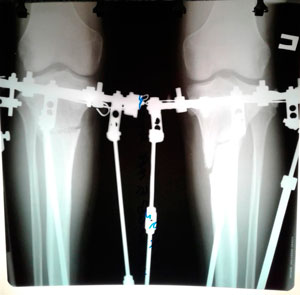

Дата операции - 18.06.2019г.

Дата снятия аппаратов - 20.09.2019.

Срок сращения - 93 дня.